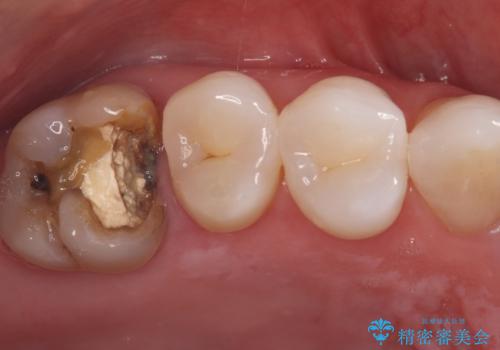

詰め物が外れた奥歯。MB2の発見

- 「奥歯の詰め物が取れた」という主訴でご来院されました。レントゲンおよび視診の結果、詰め物が外れた内部で虫歯が再発しており、根の先にも炎症が見られたため、再根管治療(根の再治療)が必要と診断しました。 特に上顎の大きな奥歯(第一大臼歯)は、通常の根管以外に「MB2」と呼ばれる隠れた根管が存在することが多く、これが未処置のままだと再発の原因となります。そこで、歯科用顕微鏡(マイクロスコープ)を用いて徹底的に内部を清掃し、その後、強度と審美性に優れたオールセラミッククラウンで修復する計画を立案しました。

顕微鏡によるMB2の発見: 歯科用顕微鏡(マイクロスコープ)を使用し、根管内を強拡大して観察したところ、事前の予想通り、従来の治療では見逃されていた**第4の根管「MB2」**を発見しました。この未処置だった根管内の汚れを徹底的に除去・消毒することで、痛みの再発リスクを根本から取り除きました。